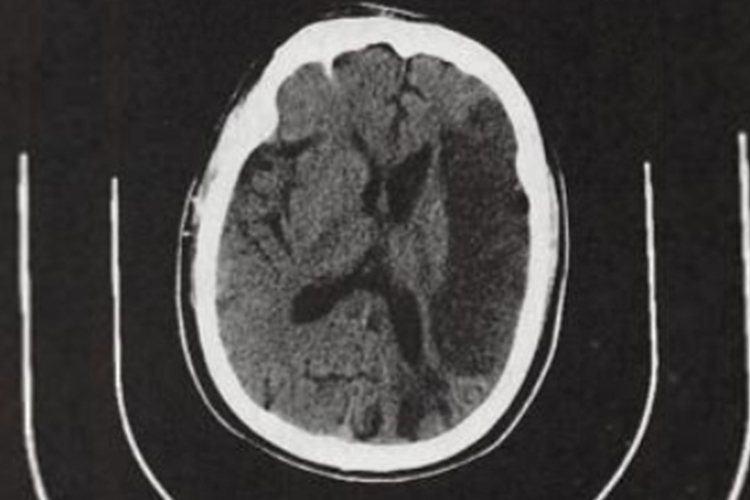

- 在脑梗发作前,身体可能会出现一些预警信号。流口水可能是其中之一,但不能仅凭流口水这一症状就确诊为脑梗的前兆。当脑部血管开始出现病变,影响到控制面部肌肉和吞咽功能的神经时,可能会导致口腔肌肉的协调性变差,从而出现流口水的现象。

- 特别是单侧流口水,且伴有嘴角歪斜、言语不清、肢体无力或麻木等症状时,需要高度警惕脑梗的可能性。然而,流口水也可能是由其他多种原因引起的。例如,口腔疾病如牙龈炎、牙周炎、口腔溃疡等,可能导致口腔分泌物增多,引起流口水。